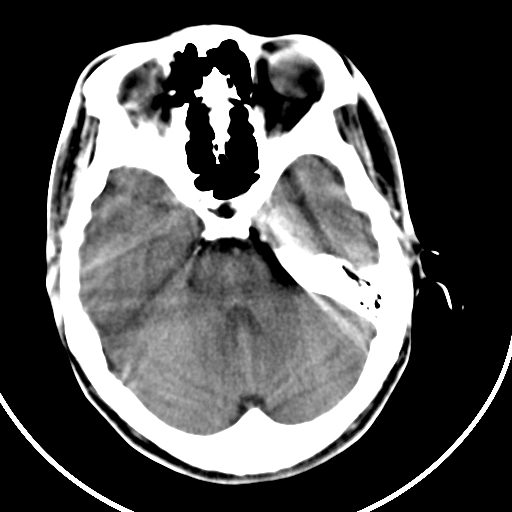

颅骨凹陷性骨折并压迫脑组织致大脑镰下疝!

硬膜外血肿机化

如果是骨折,外板正常内板这么明显凹陷,请问这样的骨折是怎样形成的?形成的机理是什么?有没有可能形成?

硬膜外血肿伴包膜钙化

考虑硬外血肿并血肿肌化? 难道是传说中的盔甲脑?

左侧额部硬膜外血肿机化、骨化。

左侧额部硬膜外血肿机化、骨化